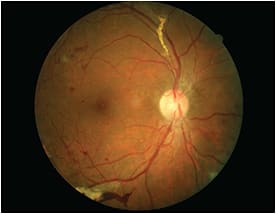

Above, a dilated exam of a 55-year-old female with Type II DM and hypertension revealed proliferative diabetic retinopathy (PDR) OD. Her last eye exam was five years ago. Had she undergone yearly diabetic eye exams, early treatment would have been initiated before the development PDR.

DR and its associated pathology, including diabetic macular edema (DME), remain the most important ocular complications of DM. In some cases, DR is the initial sign of underlying disease in more than 21% of type 2 DM patients, reports the ADA.